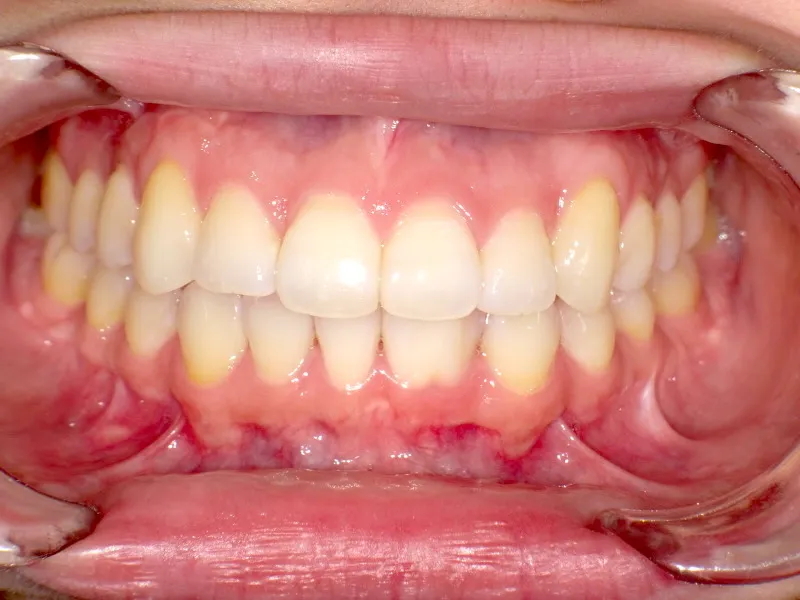

八重歯で笑うと尖った歯が目立ちます。

上下ガタガタで、下の歯は癒合歯(2本がくっついて1本の歯)です。

治療前と治療後で下の歯の銀歯がなくなっています。

これは銀歯の第1大臼歯を抜いて第2大臼歯、第3大臼歯の親知らずを使いました。

治療回数71回、3年5ヶ月の治療期間で矯正治療を終了しました。

主訴が改善され、ご満足頂きました。